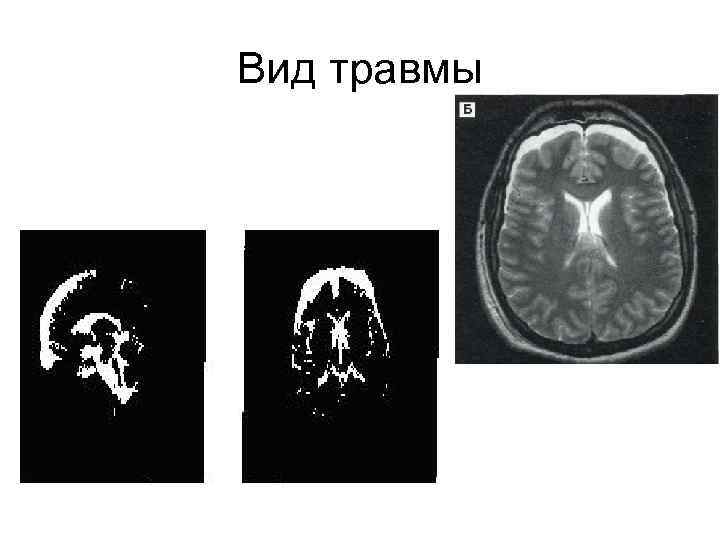

Вид травмы